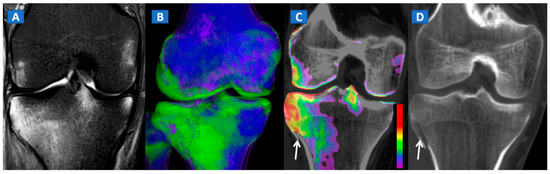

Figure 7.

A 44-year-old male with post-traumatic OCL of the talar dome. On the coronal STIR MRI image (A), a hyperintense subchondral area of BME is depicted on the medial aspect of the talar dome (arrow), which is consistent with the diagnosis of OCL of the talus. The lesion appears hypointense on the T1-weighted images ((B); arrow). On the 1 mm reconstructed 2D coronal DECT image (C) and coronal 3D DECT map, the lesion appears as a subchondral oedematous area (arrow), due to its increased water content. On the corresponding 3D image (D) the BME is coded in green (arrow).